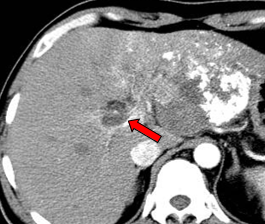

现病史:2011年01月4日于当地医院行PET/CT: 1. 肝左外叶肝癌并肝门区淋巴结转移,2. 下腔静脉及右心房结癌栓,考虑为”原发性肝癌“。

肝左叶巨块型肝癌(13.8cm×9.1cm),伴肝右后叶子灶,门静脉左支、肝左静脉及下腔静脉内癌栓。

2011-02-12复查CT示:肝左叶碘油散在沉积,病灶大部分仍有活性,肝右后叶病灶未见碘油沉积;门静脉癌栓较前进展,累及主干及右支;肝左静脉及下腔静脉内癌栓无明显变化。AFP:26802 ng/ml。

2011-04-20复查CT示:肝左叶病灶较前缩小,肝右叶病灶见碘油致密沉积;门脉癌栓左支较前缩小,右支癌栓消失;下腔静脉、肝左静脉癌栓消失。AFP:4983 ng/ml。